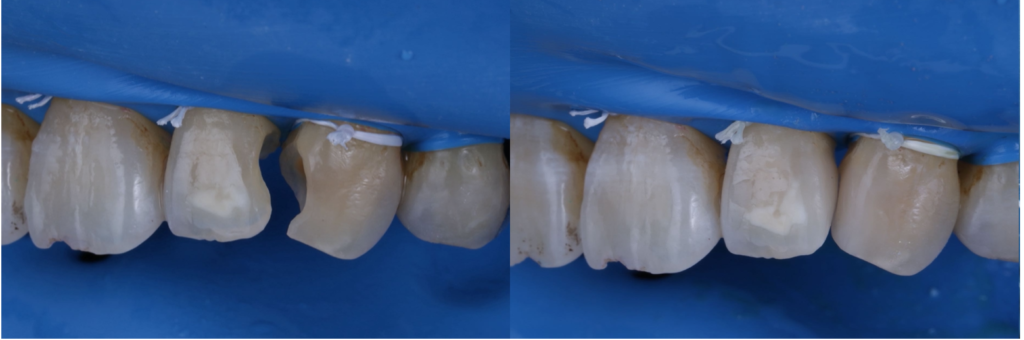

歯の白濁が気になる方へ|削らずに改善を目指す「ICON(アイコン)治療」

最近、「歯の白濁が気になる」「前歯の白い斑点が目立って笑いづらい」と感じていませんか?鏡を見たときや写真に写った自分の歯を見て、違和感を覚えたことがある方は意外と多いものです。歯の白濁は痛みがないことがほとんどですが、見た…